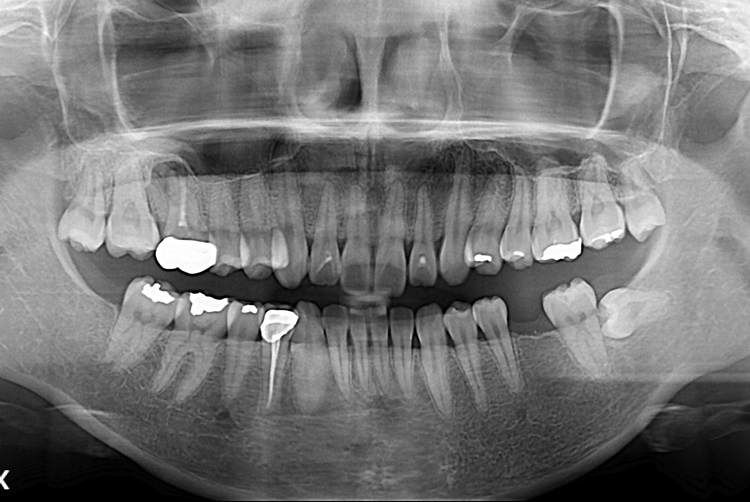

[임플란트] 어금니 임플란트

치료후 : 2019-05-03

세종치과는 많은 환자와 다양한 케이스를 바탕으로

항상 편안한 임플란트 수술을 제공하고자 노력하고,

오래동안 튼튼히 쓸 수 있는 임플란트 수술을 가장 큰 목표로 삼고 있습니다.